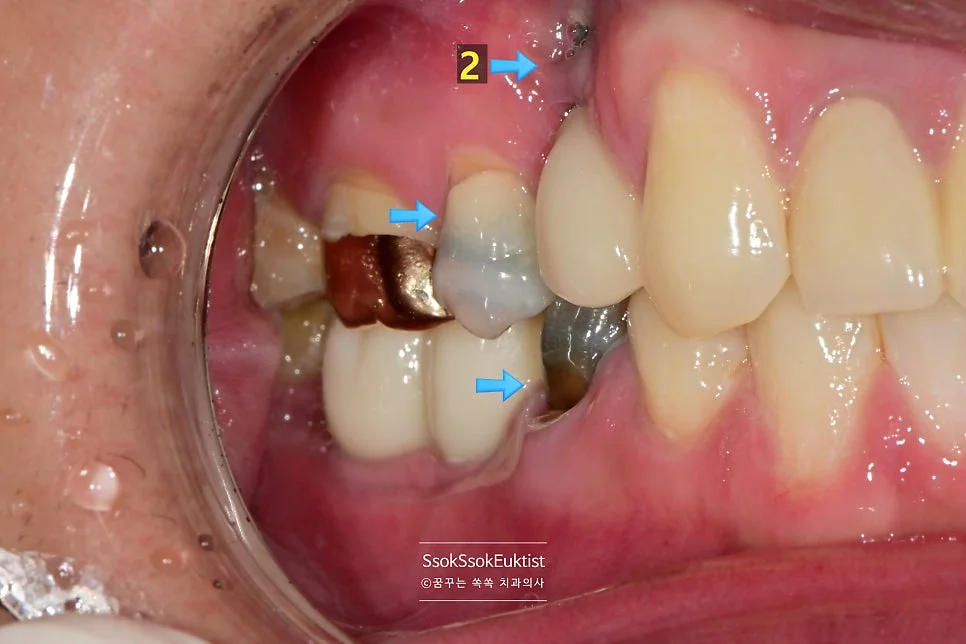

그런데 2번의 임플란트를 한번 보면 뭔가 잇몸이 부자연스러운 것을 볼 수 있는데요.

임플란트 주변에 뼈가 다 녹아내리고 그 바깥에 잇몸까지 혈류를 받지 못해 점점 괴사하고 있는 모양새입니다.

임플란트가 뼈와 유착에 성공은 하였다 하더라도 임플란트를 감싸고 있는 뼈가 부족하면 이렇게 점점 임플란트 주위염으로 뼈와 잇몸이 녹아내리게 되는데요.

이래서 임플란트는 가급적 깊게 그리고 입천장(혀) 쪽으로 위치하여 식립하여야 합니다.

이 임플란트는 점점 염증이 심해질 것이고 그나마 남아 있는 잇몸까지 녹게 되면 이후의 치료가 너무 어려워지기에 임플란트를 제거한 후 재식립을 시도합니다.